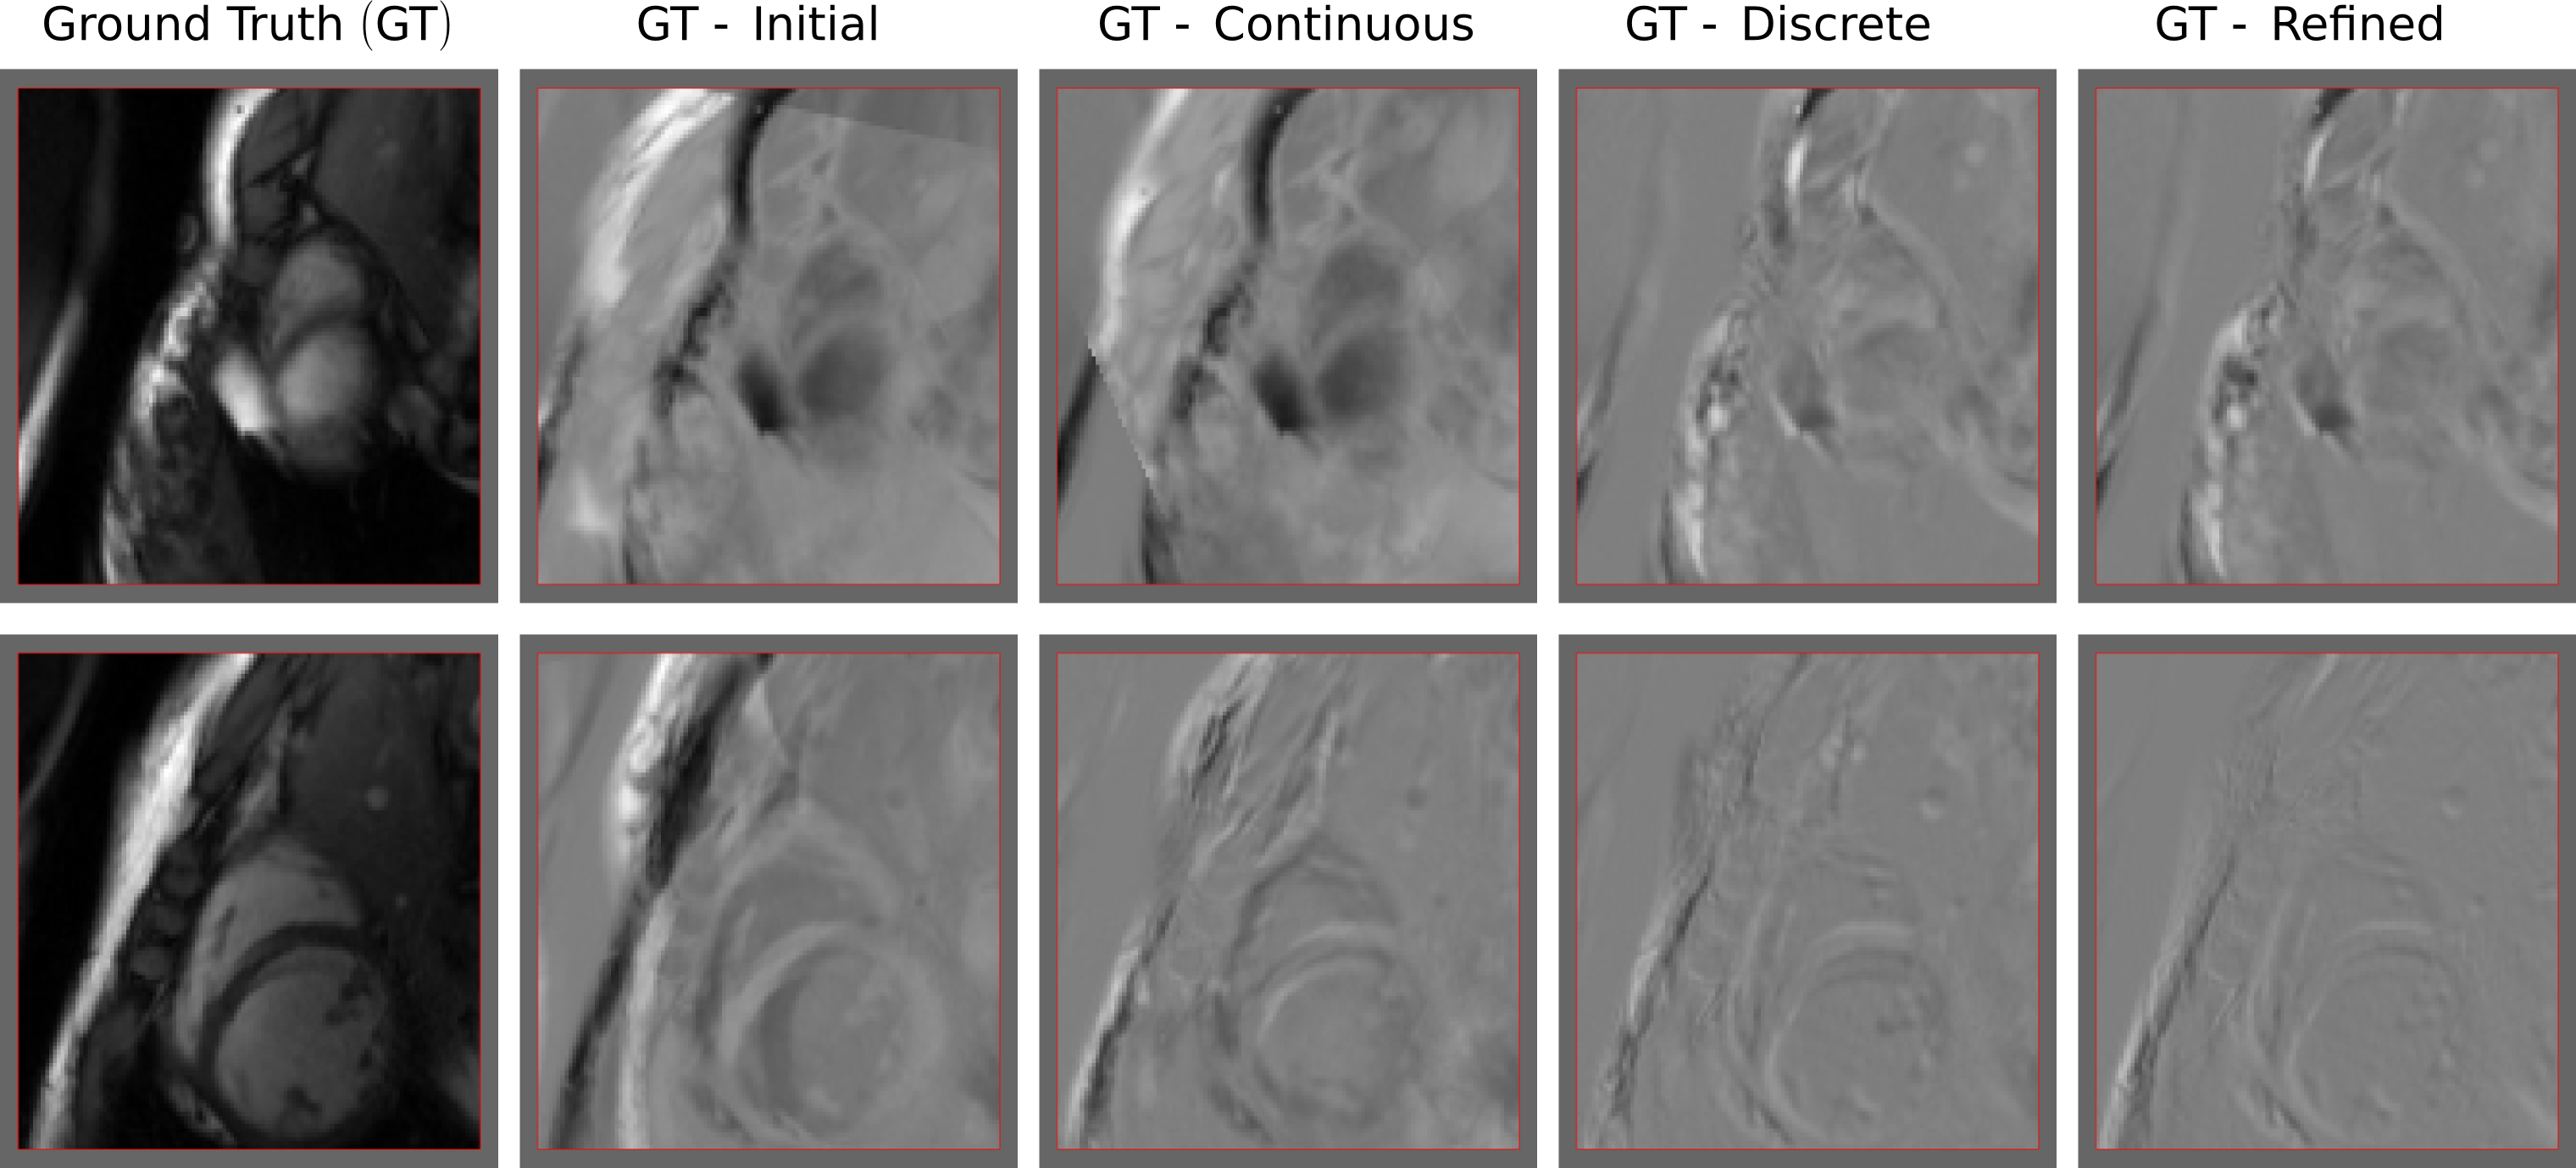

Refer to caption

Figure 2: Visual results for two slices of the individual tests. The first column corresponds to the input 2D slice. The second column shows the difference between the input 2D slice and the initial slice. The other columns show the difference between the input and the one resulting slices applying simplex, discrete and refined approaches. Grey values indicate no difference, while white and black value indicate inconsistencies. As it can be observed, the solution given by the refined approach is outperforming the others.

Individual tests. The first set of experiments measures the accuracy of the three approaches using individual tests, where 100 random slices extracted from the 20 volumes are considered as single images (independently of the series), and registered to the first volume M0subscript𝑀0M_{0}. We run the same experiment for every slice using three different initializations (resulting in 300 registration cases), where ground truth parameters were randomly perturbed in three different ranges ([5, 12), [12, 18), [18, 25) millimeters for translation and [0.1 , 0.2), [0.2, 0.3), [0.3, 0.4) radians for rotation parameters) to guarantee that both, good and bad initializations, are considered for every slice. Quantitative results are reported in Figures 3, 4 and summarized in Table 1. Visual results for qualitative evaluation are reported in Figure 2.

Results in the scatter plot from Figure 3 indicate that, as we go farther away from the initialization (in this case, it is quantified by the MAD between the input 2D image and the slice corresponding to the initialization), discrete and refined methods tend to be more robust. This robustness is clearly reflected by the slope of the trend lines: the refined method presents the trend line with the lower slope, meaning that even for bad initializations it converges to better solutions. The boxplot from Figure 4 and the numerical results from Table 1 confirm that discrete and refined methods perform better not only in terms of MAD, but also with respect to the distance between the rotation/translation estimated and ground truth parameters.